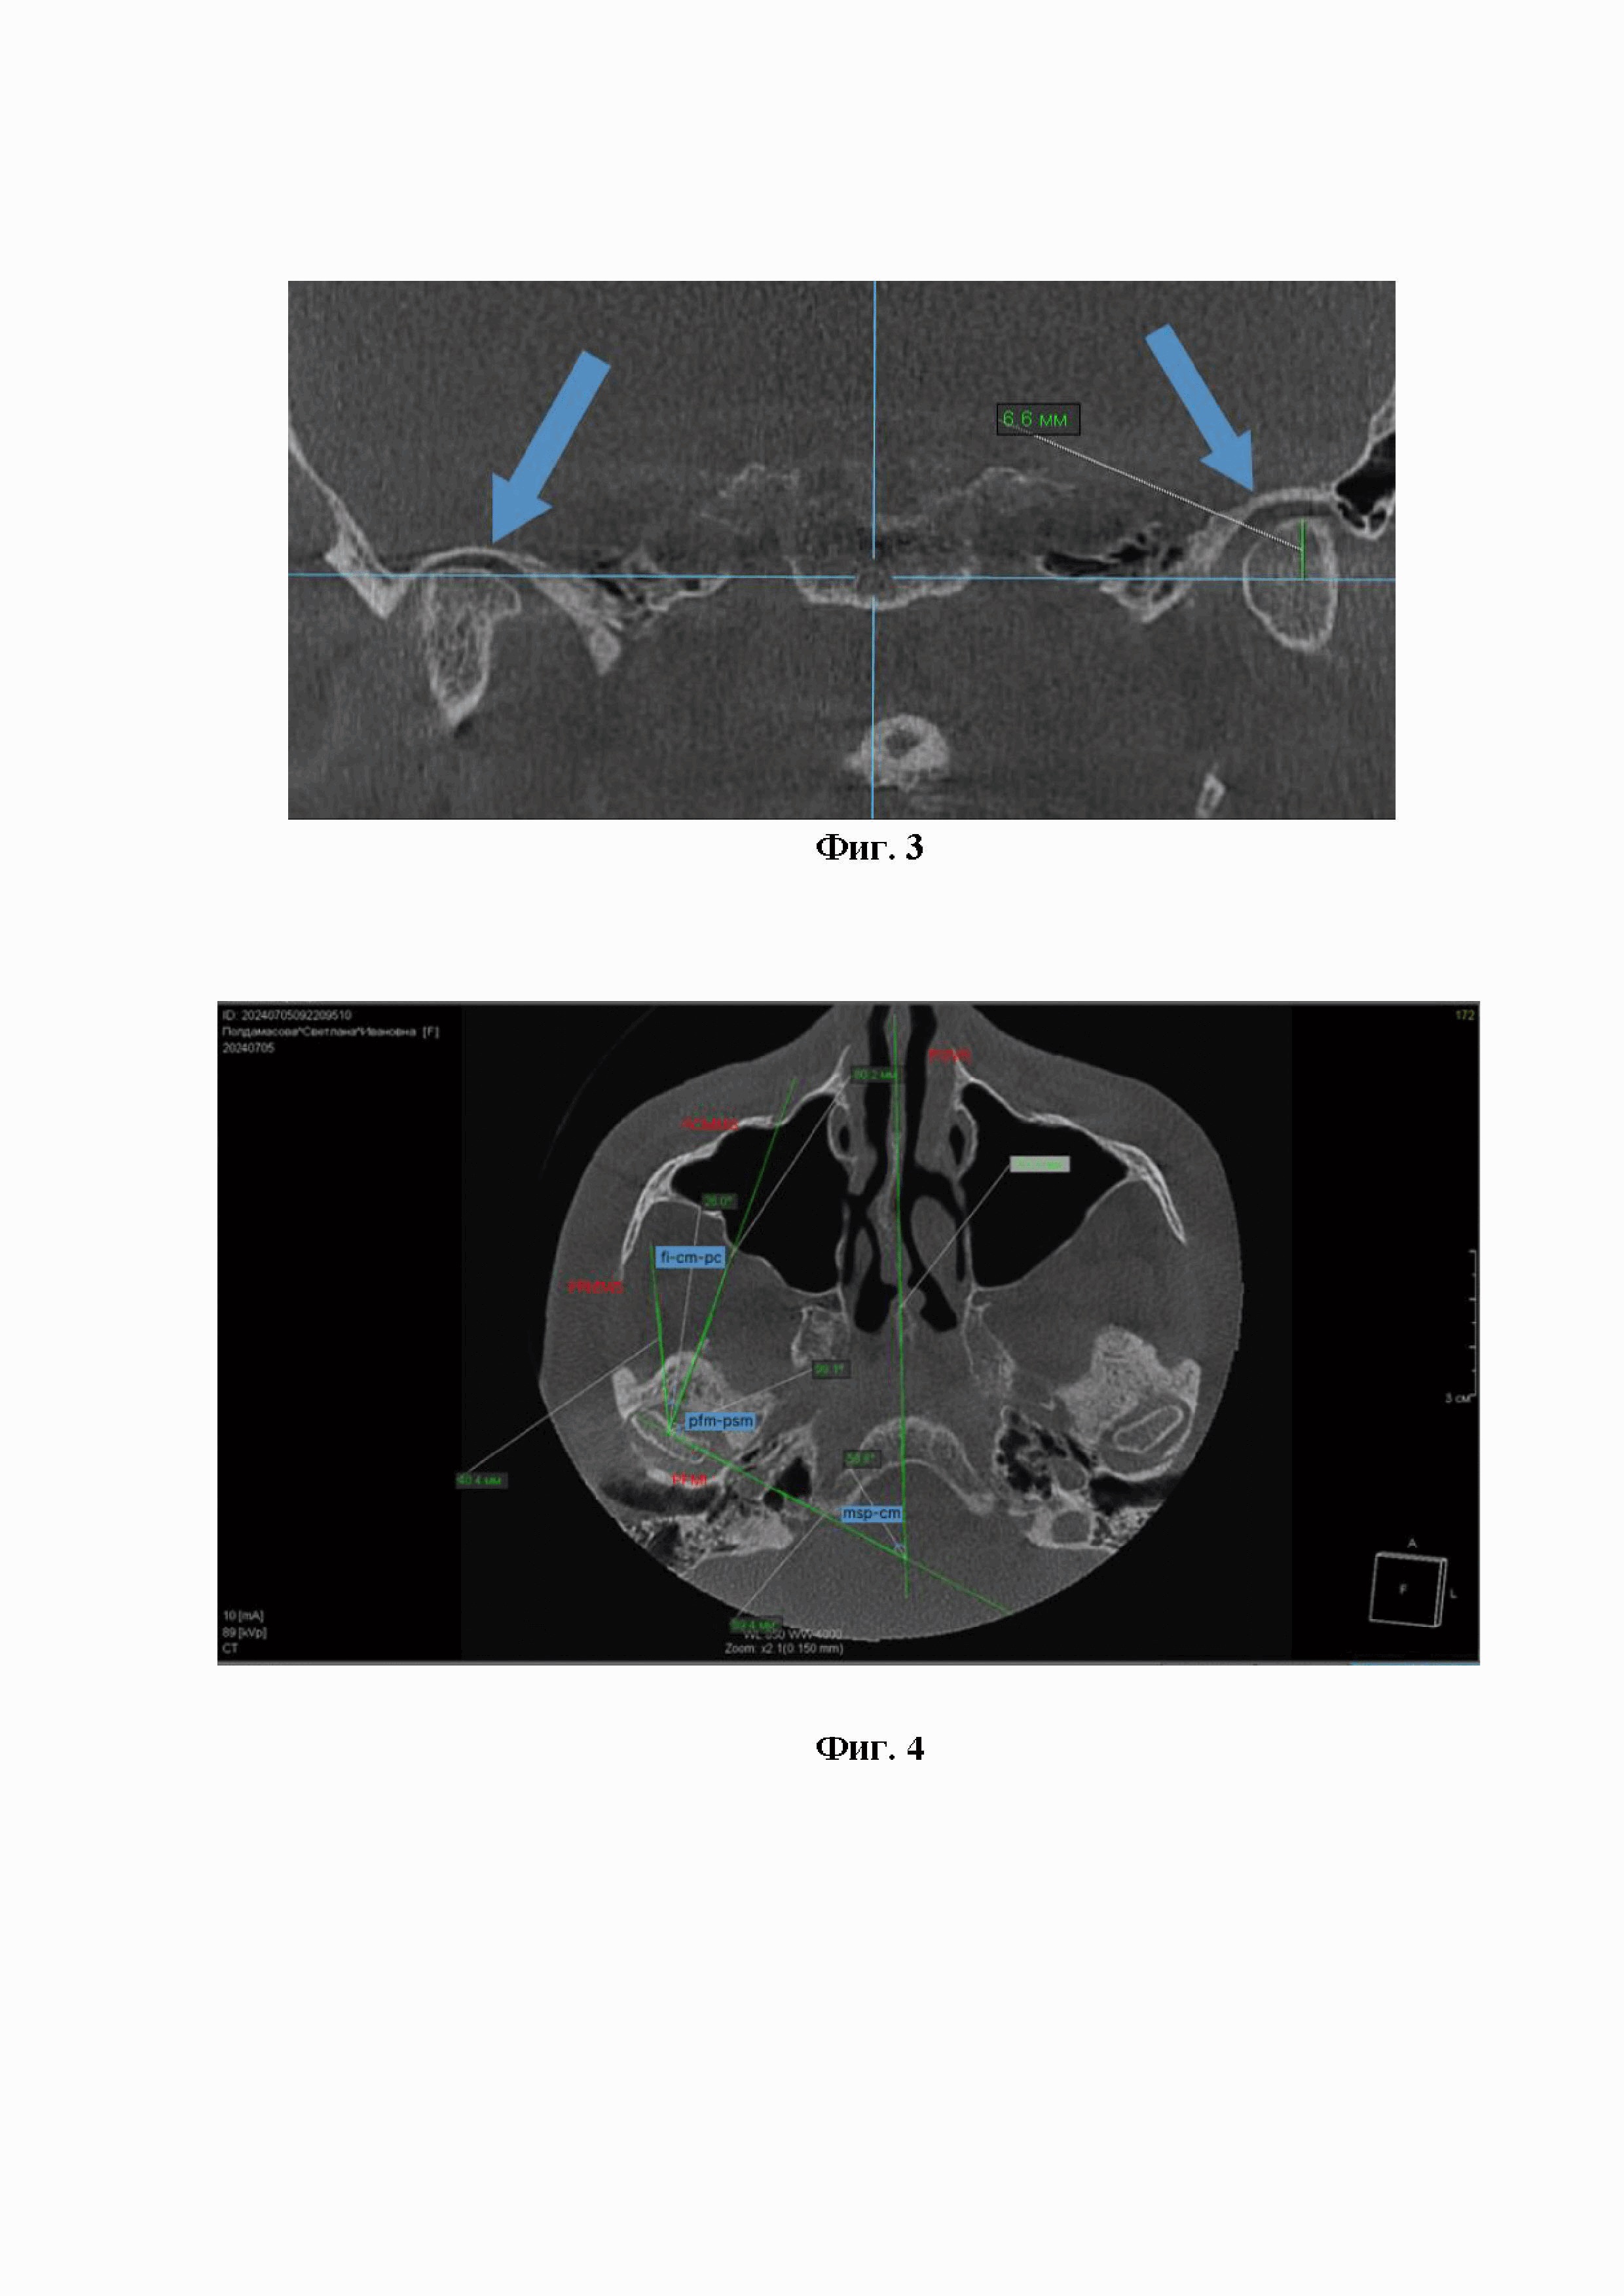

Клинический пример 2. Способ определения положения головки нижней челюсти в пространстве нижнечелюстной ямки височной кости по краниометрическим показателям, выявляемые методом конусно-лучевой компьютерной томографии костей черепа и построение вписанных в анатомическое образование окружностей для определения мезио-дистальных размеров головки.

Пациентка П., 67 лет, обратилась с жалобами на болезненность в области ВНЧС справа, невозможность открывания полости рта. Диагноз: дистальное положение головок нижней челюсти, не вправляемый вывих диска ВНЧС.

На КЛКТ нижней челюсти в сагиттальной проекции видно дистальное положение головки в нижнечелюстной ямке височной кости справа, сдавление сосудисто-нервного пучка (фиг. 2). Дистализация правой головки нижней челюсти составляет 6.6 мм (фиг. 3).